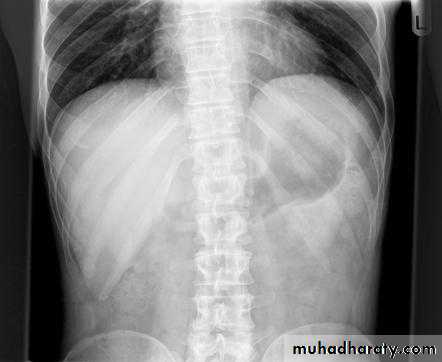

Pneumoperitoneum

Defined as free gas in the peritoneal cavityThe commonest cause is perforated peptic ulcer and two-thirds of such cases are recognizable radiologically

Pneumoperitoneum under the right hemidiaphragm is usually easy to recognize, but free gas under the left hemidiaphragm is difficult to recognize because of the overlapping gas shadows of the stomach and splenic flexure.

Gas under the diaphragm is much easier to diagnose on an erect chest film than on an upright abdominal film